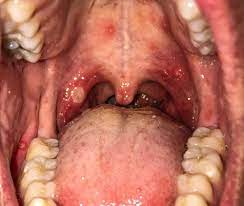

Roof of your mouth pain could be due to inflammation from infection or an allergic reaction or may be caused by irritants like smoking dental trauma or eating certain foods.

Roof of mouth pain questionnaire Use our free symptom checker to find out whats causing your pain. Pain can also happen from irritants like dental trauma smoking or eating certain foods. Signs of an allergic reaction often are present in the mouth and tongue and also can even reach the throat. If it is one bump in the same place you probably have a block salivary gland yes they are all over your mouth–even the roof of the mouth. Roof of mouth pain questionnaire Use our free symptom checker to find out whats causing your pain. While you could simply stop eating bananas and be safe it is best to have any severe food reaction properly diagnosed in this case i.